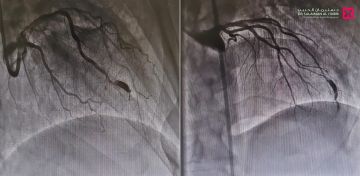

وقال د. فيصل الصميدي استشاري أمراض القلب وقسطرة الشرايين ورئيس الفريق الطبي المعالج، أن المراجع ظل يعاني منذ سنوات من ألم في منتصف الصدر، والإرهاق وحرقة المعدة والغثيان وضيق النفس، ومؤخراً تزايدت حدة هذه الأعراض، وأثرت على نمط حياته اليومية، فراجع المستشفى وأجريت له سلسلة من الفحوصات الطبية، كاختبار الجهد وتخطيط القلب والأشعة الصوتية، وقد أظهرت النتائج وجود انسدادات بالشرايين التاجية للقلب، ومن ثم خضع لقسطرة استكشافية أظهرت بدورها وجود توسع شديد في الشريان التاجي الأمامي، وسبب التوسع نقصاً في التروية في بعض أجزاء القلب، مما أثر على أجزاء معينة من عضلة القلب.

وتابع قائلاً أن الفريق الطبي قام بعد دراسة الحالة، ووضع خطة علاجية متكاملة تناسب حالة المراجع، وأجرى عملية متقدمة بتقنية القسطرة القلبية، تم فيها إزالة الانسدادات عن الشرايين التاجية، كما تم عمل إجراء طبي غير جراحي لسد التوسع الشديد في الشريان التاجي، عن طريق القسطرة التاجية 'COILING' بالدخول عبر الشريان الفخذي، وتعمل هذه التقنية على سد التمدد ومنع تدفق الدم إليه، مما يقلل من خطر انفجاره، وهي تتميز بالفعالية العالية، ولا تتطلب شقوق جراحية كبيرة، وتجرى تحت التخدير الموضعي، إضافة إلى أنها أكثر أماناً وأقل مضاعفات مقارنة بالجراحة التقليدية.